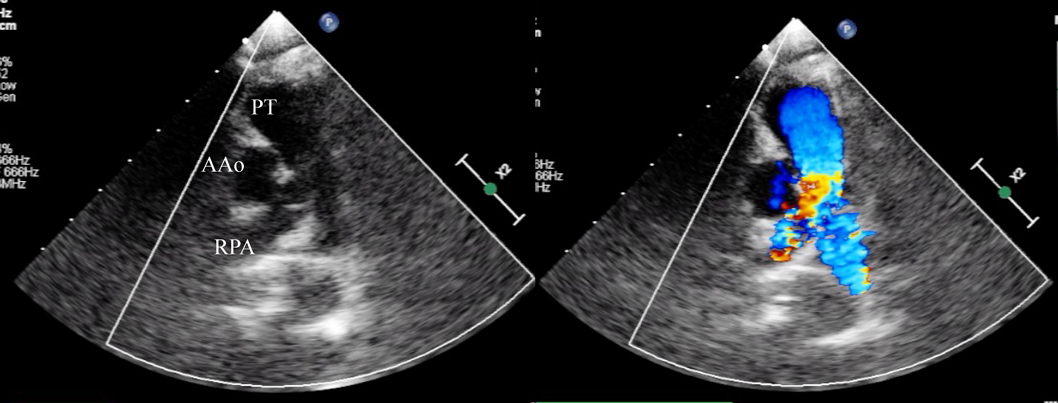

A female baby was delivered by an emergent cesarean section secondary to fetal bradycardia at a gestation of 33 weeks and 4 days. She weighed 1,700 g, and was eventually referred to our hospital at 12 days old. During pregnancy, her mother was doing well without detection of any congenital anomaly including heart disease on routine fetal ultrasonograms. She had no family history regarding congenital heart disease. She was suffering from progressive respiratory distress and congestive heart failure. Levine 2/6 continuous murmur was heard at the left sternal border of the second intercostal space. Her heart rate, respiratory rate and blood pressure were 164 beats/min, 70 breaths/min and 60/30 mmHg, respectively. Oxygen saturation was 99% on room air. Chest X-ray showed cardiomegaly with right pulmonary plethora (Fig. 1). An electrocardiogram showed biatrial overload. Her serum B-type natriuretic peptide level was 3,383 pg/mL. The RPA originated from the left posterior aspect of the proximal AAo. The orifice of the RPA at the proximal AAo was 5.0 mm. Moreover, the RPA was connected to the PT via a 2.0 mm-diameter lumen at the intrapericardial portion adjacent to its aortic origin. She was diagnosed as having AORPA, left aortic arch, patent ductus arteriosus bridging normally between the aortic arch and the PT, and patent fossa ovale by transthoracic echocardiography and computed tomography (Figs. 2, 3). Nitrogen inhalation therapy was started to treat high pulmonary flow.

Fig. 1 Preoperative chest X-ray showed cardiomegaly and right pulmonary plethora